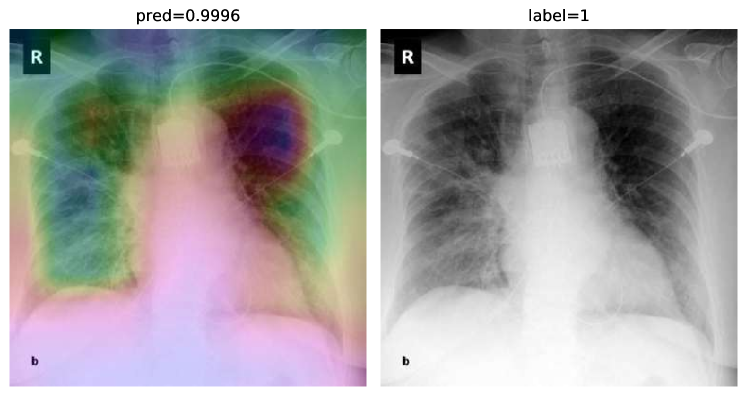

To overcome the aforementioned issues and force the model’s attention to the correct regions of interest (ROIs), we introduce the COVID-CXNet. Our model is initialized with the pretrained weights from CheXNet. A dataset of 3,628 images, 3,200 normal CXRs and 428 COVID-19 CXRs, are divided into 80% as training-set and 20% as test-set. Batch size is set to 16, rather than 32 in previous models, regarding memory constraints. Grad-CAMs of the COVID-CXNet for random images are plotted in Fig. 15.

Figure 15: Grad-CAM visualization of the proposed model over sample cases

More Grad-CAMs are available in Appendix A. Heatmaps are more accurate than previous models, while an accuracy of 99.04% and an f-score of 0.96 are achieved. Table 3 is the confusion matrix of the proposed model.